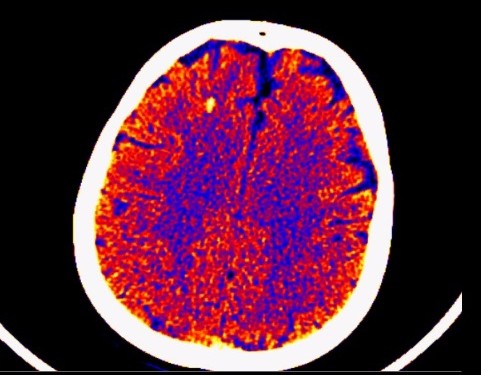

Bilgisayarlı Beyin TomografisiHead Colour CT

Aşağıda kemik penceresi verilmiş olan Beyin BT ‘yi nasıl yorumlarsınız?

Yukarıdaki Beyin Tomografisinde ne görülmektedir? ÜSYE ile beraber devam eden ateş yüksekliği olan hastada, bilinç değişikliği başlamıştır. Yukardaki beyin tomografisi...